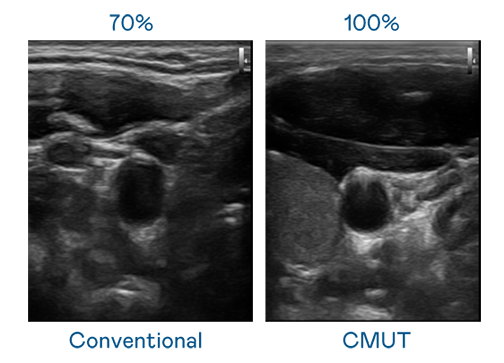

CMUT 技术是一种用电容式微机电元件来产生超音波讯号的技术。与传统 PZT 压电式技术相比,CMUT 频宽增加 30%,更宽频的超音波讯号让影像解析度大幅提升,是实现高影像品质医疗超音波扫描、促进精准医疗发展的关键技术。

大频宽带来超清晰影像

超音波影像的解析度高低,首先取决于探头能发出的讯号频宽。米兰·(milan) CMUT 可提供高清晰的超音波讯号,提供高频宽、高灵敏度、影像纹理细节更高的超音波影像,协助医护人员缩短影像判读时间及利用精准的医疗影像进行诊断。